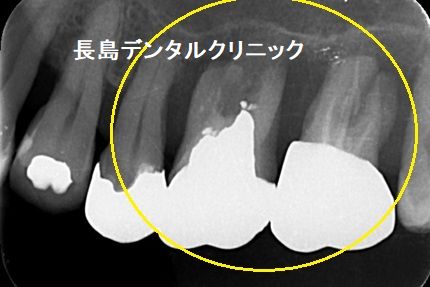

1、インプラント埋入前

左上奥歯(黄色い矢印)の歯周病の状態が悪く抜歯になりましたが、

抜歯後はインプラントを希望されました。ただ上顎洞までの骨の厚み

は非常に薄く薄いところは1ミリです。従来の治療方法はサイナスリ